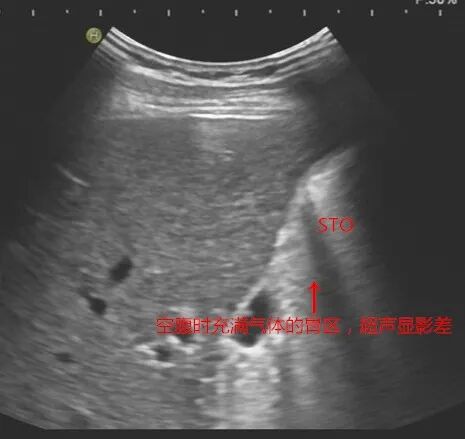

▲空腹的胃内有气体,传统超声无法检查